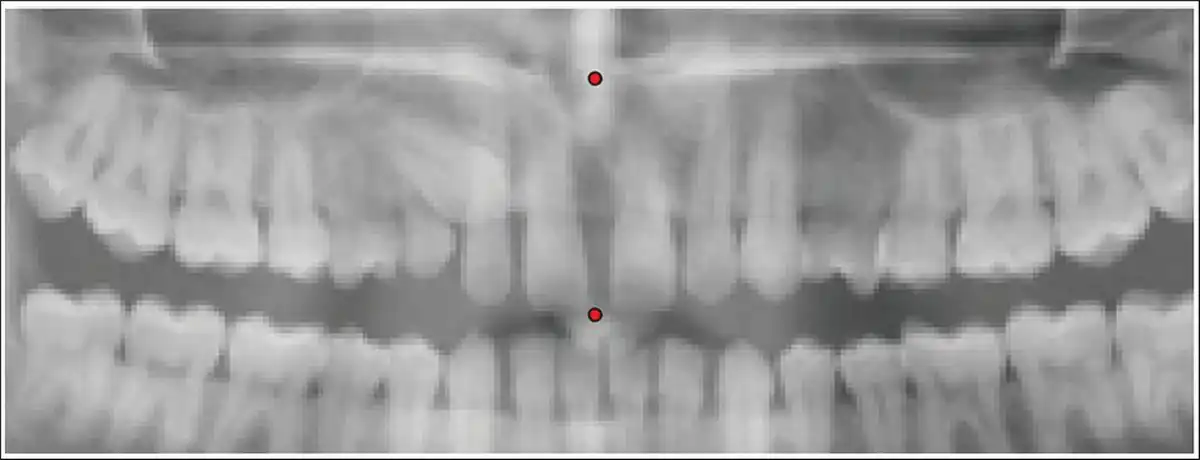

Step 2: Two points (anterior nasal spine and contact point between two maxillary central incisors) were marked to generate the midline (Figures 4 and 5).

Points for Generation of Midline.

Generation of Midline.